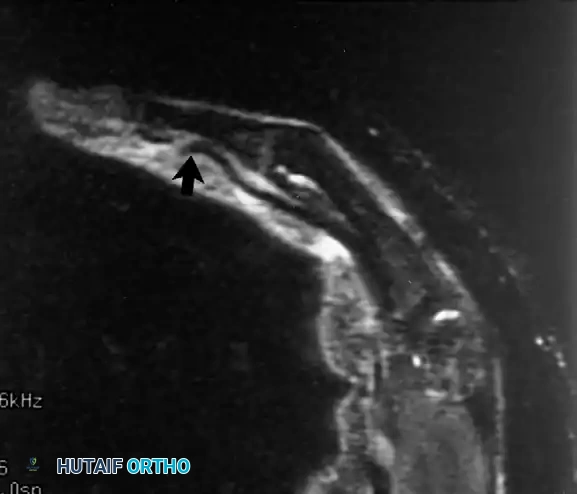

يعاني المريض من ألم شديد وتورم في الجزء الخلفي من الكوع، مع عدم القدرة على فرد الذراع ضد المقاومة. يؤكد الرنين المغناطيسي التشخيص من خلال إظهار انفصال الوتر عن مكان اتصاله بعظمة الناتئ الزجي في الكوع، مع وجود سوائل تملأ الفجوة بين الوتر والعظم.

أشعة الرنين المغناطيسي تظهر انفصال وتر العضلة ثلاثية الرؤوس عن عظمة الناتئ الزجي